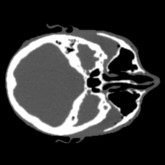

Cone-beam CT (CBCT) employs a flat-panel detector to achieve three-dimensional imaging with high spatial resolution. However, CBCT is susceptible to scatter during data acquisition, which introduces CT value bias and reduced tissue contrast in the reconstructed images, ultimately degrading diagnostic accuracy. To address this issue, we propose a deep learning-based scatter artifact correction method inspired by physical prior knowledge. Leveraging the fact that the observed point scatter probability density distribution exhibits rotational symmetry in the projection domain. The method uses Gaussian Radial Basis Functions (RBF) to model the point scatter function and embeds it into the Kolmogorov-Arnold Networks (KAN) layer, which provides efficient nonlinear mapping capabilities for learning high-dimensional scatter features. By incorporating the physical characteristics of the scattered photon distribution together with the complex function mapping capacity of KAN, the model improves its ability to accurately represent scatter. The effectiveness of the method is validated through both synthetic and real-scan experiments. Experimental results show that the model can effectively correct the scatter artifacts in the reconstructed images and is superior to the current methods in terms of quantitative metrics.